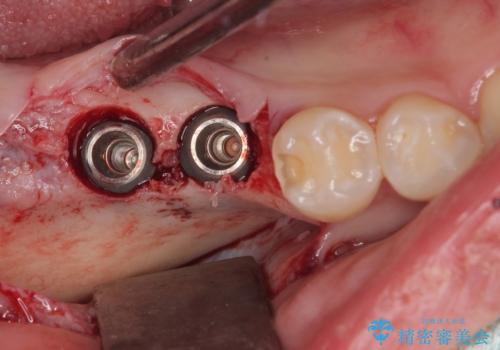

スペースが整った段階で、右下の第一大臼歯と第二大臼歯にインプラントを埋入。